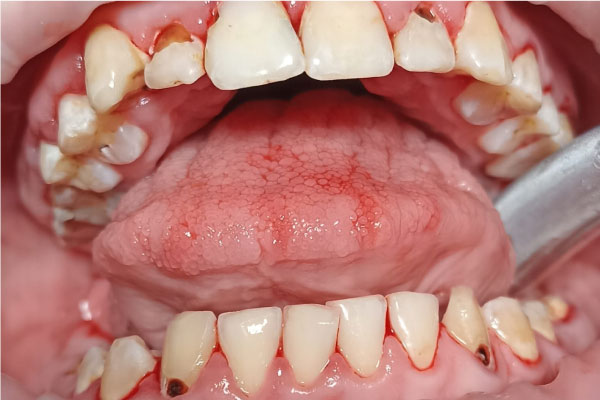

Фото ДО

Фото ПОСЛЕ

Профессиональная гигиена молочных зубов